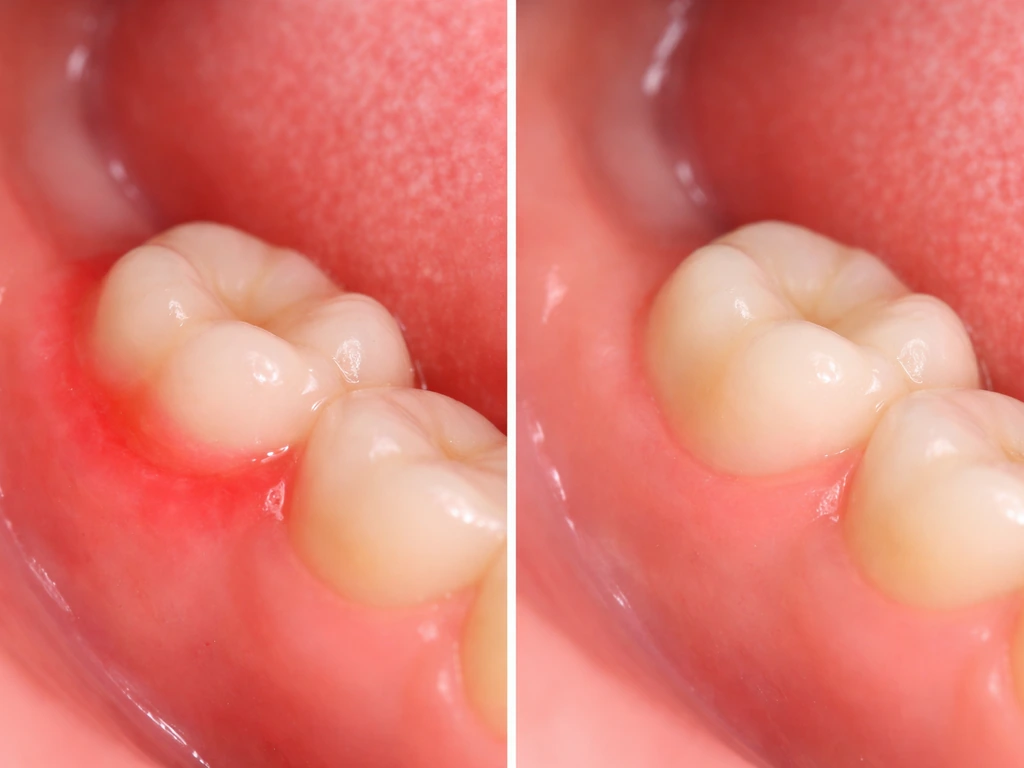

Oral hygiene as a growth enabler

Inflamed, infected gum tissue is a real obstacle to smooth eruption. Bacteria-laden gums become swollen and fibrotic, and a tooth trying to push through thick, infected tissue has a harder time of it. Brushing twice daily with a fluoride toothpaste, flossing, and using a soft toothbrush around erupting areas keeps the tissue healthy and more cooperative. If you have a tooth actively trying to come in, keep the area especially clean to prevent pericoronitis, which is an infection of the gum flap over a partially erupted tooth, a common and painful problem with wisdom teeth.